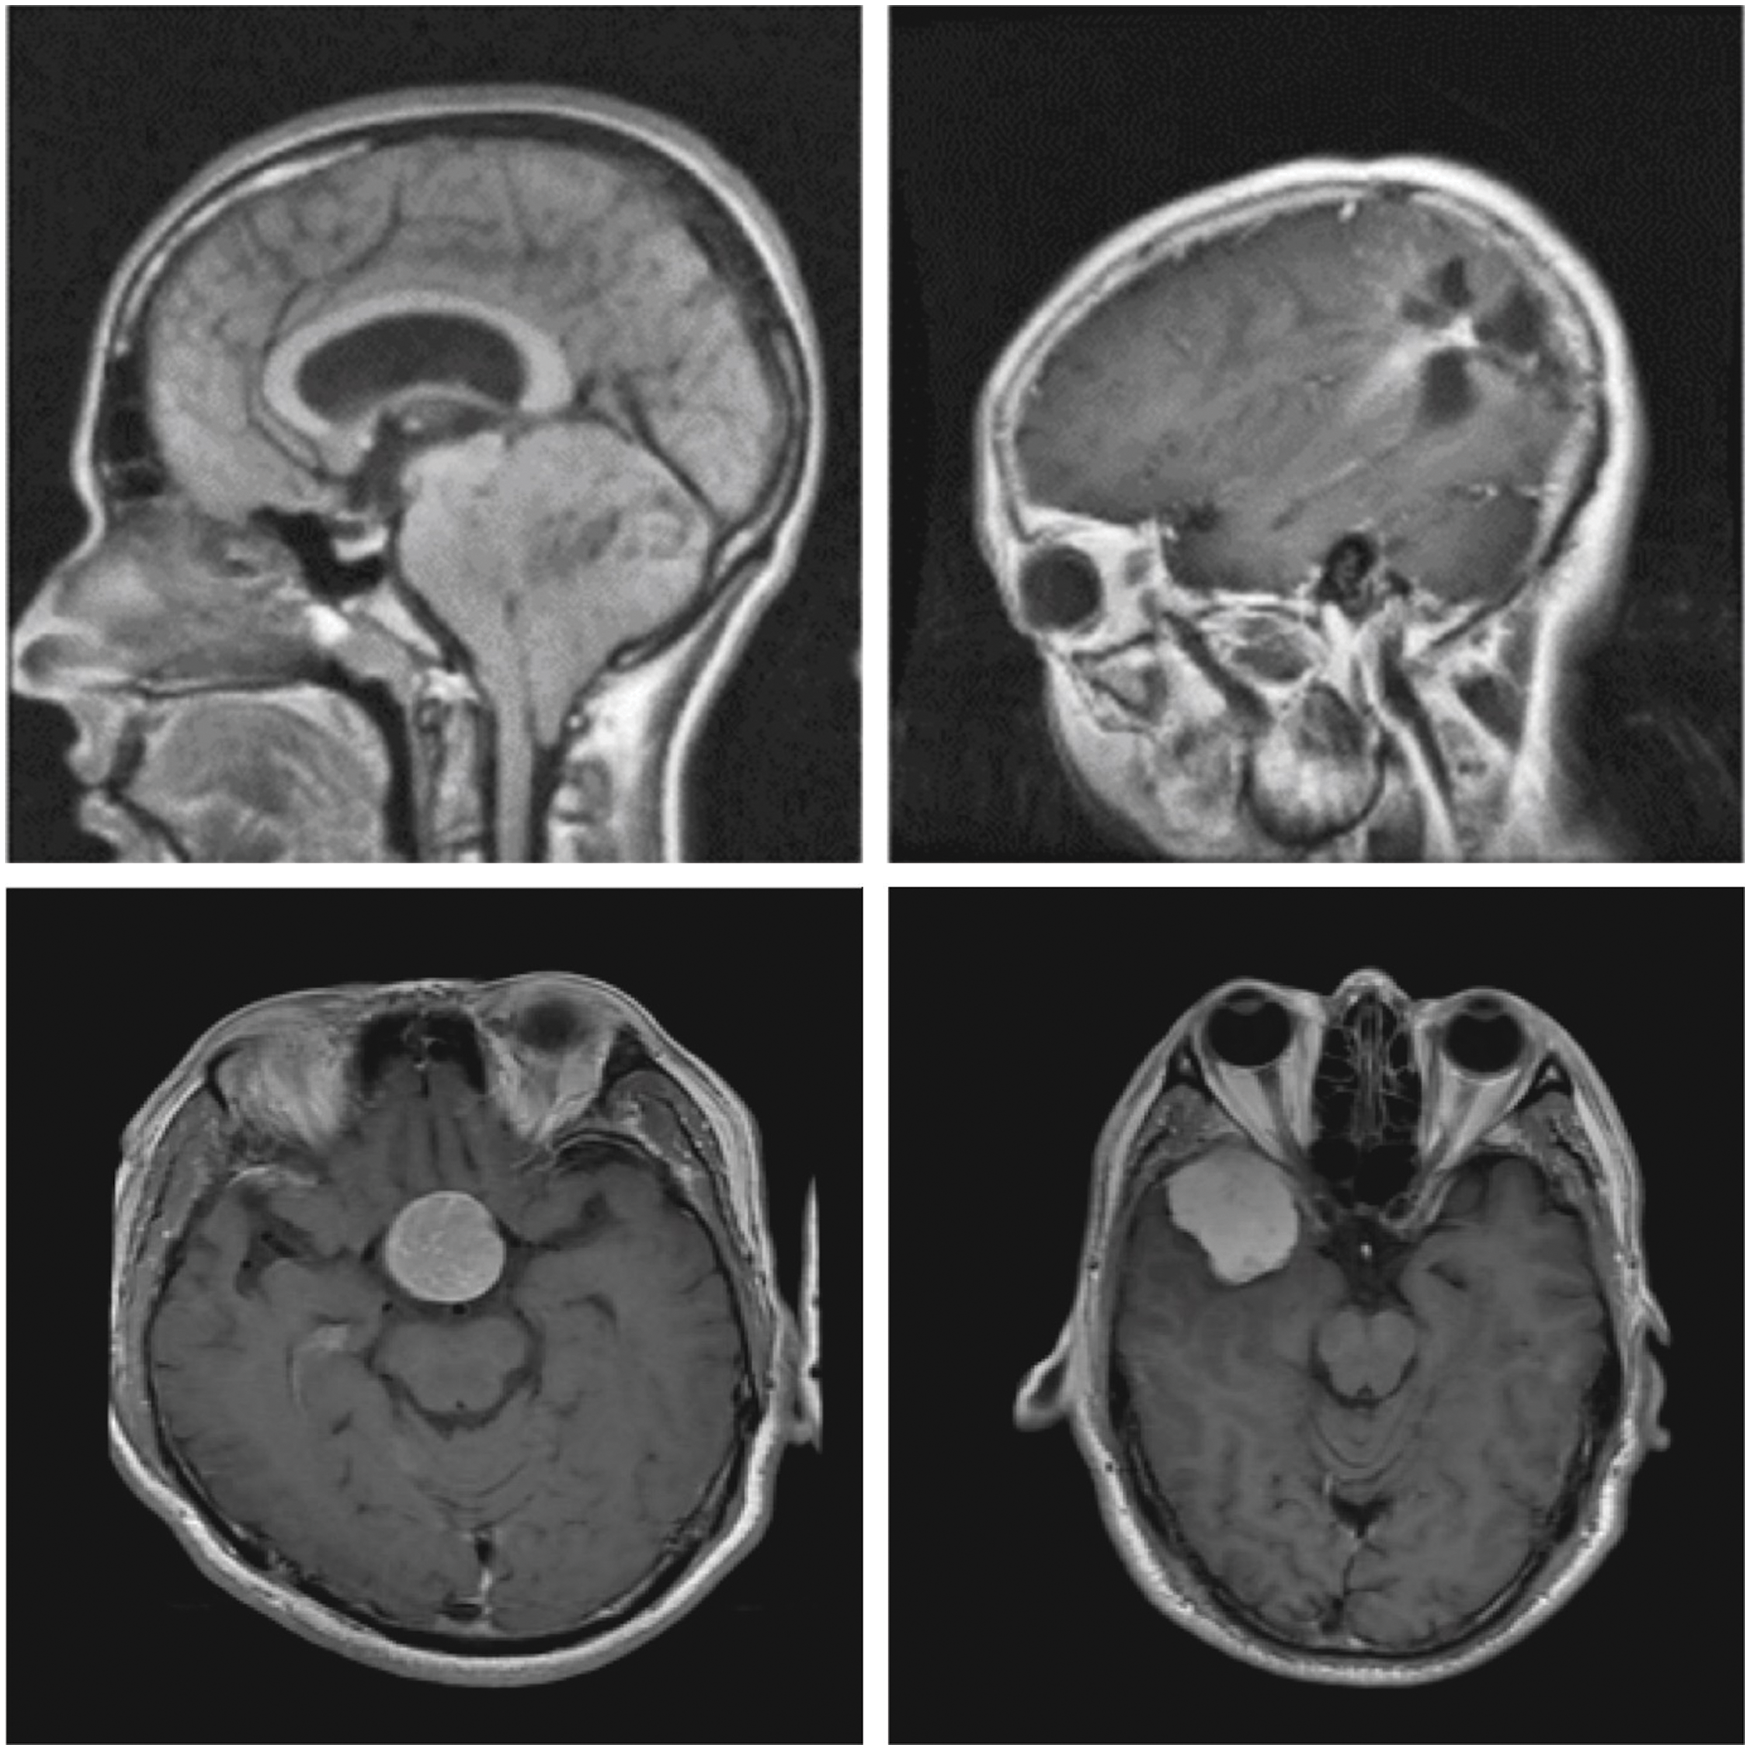

In order to establish the effective characteristics of the proposed DLBTDC-MRI model, a detailed experimental validation process was conducted using Figshare dataset [20]. It contains images under three classes and has a total of 150 images under Meningioma (MEN) class, 150 images under Glioma (GLI) class, and 150 images under Pituitary (PIT) class. Fig. 3 demonstrates some of the sample test images.

Figure 3: Sample images